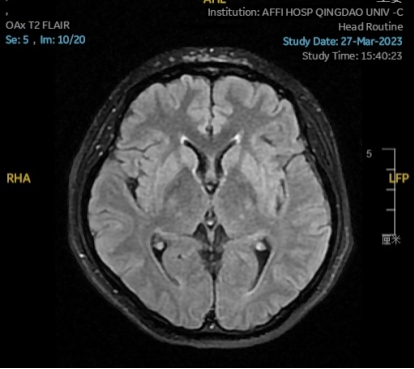

2023.03.27颅脑MR平扫示双侧基底节区及桥脑异常信号,考虑渗透性脱髓鞘综合征,较前范围略减小,请结合临床,见图4。

图4 2023.03.27双侧基底节区及桥脑见对称性片样长T1长T2信号,FLAIR呈高信号,较2023-02-24MR所示范围减小。脑室、脑池、脑沟、脑裂未见明显异常,中线结构居中。